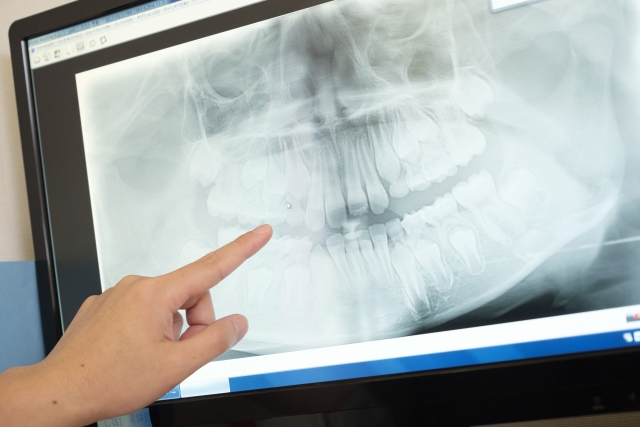

歯科医療の学問的には、入れ歯を使用していない健全な歯が多く残っている人に比べ、入れ歯を使用している人は咀嚼能率が少なからず低下します。

「入れ歯の名人」と言われた歯医者が作成した入れ歯でも、健全な歯を持った人の歯と比較するとかみ砕く効率は30~40%になると言われています。ですが、だからといって「入れ歯では何でも食べられない」と断言してしまうのは違うと考えます。

入れ歯を装着し少しでも咀嚼能率を高めて、口腔機能の低下を防げるよう、普段 歯医者は患者さんのお手伝いをしています。学問的に裏づけられた数字は説明する際に説得力がありますが、入れ歯を語る時にはそれが全てではありません。